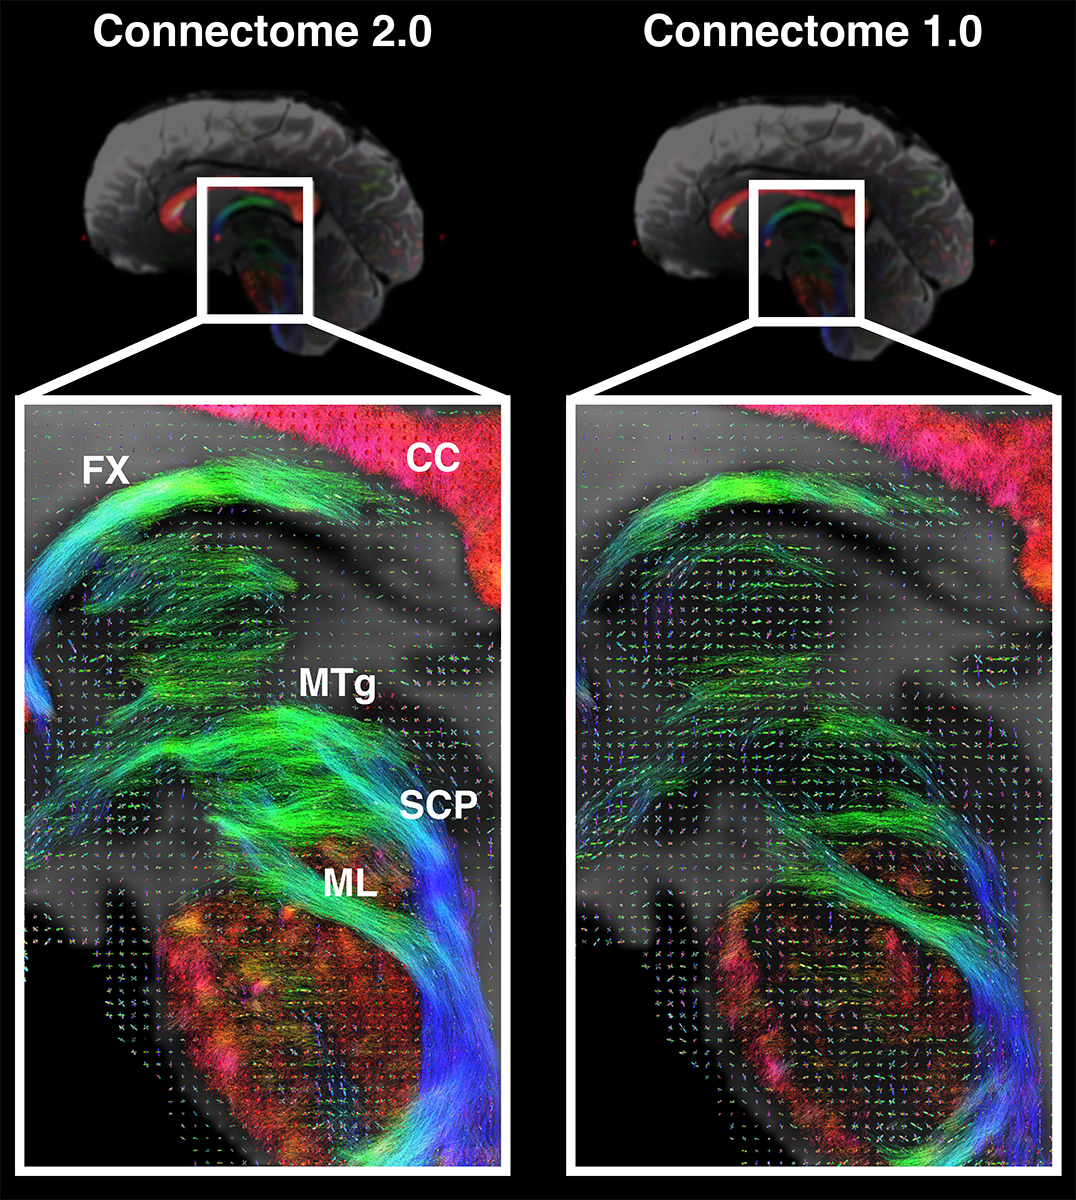

Scientists supported by NIH have developed the Connectome 2.0, an ultra-high-resolution MRI scanner capable of noninvasively imaging microscopic brain structures, advancing our ability to map the brain's wiring and understand neurological disorders at a cellular level.